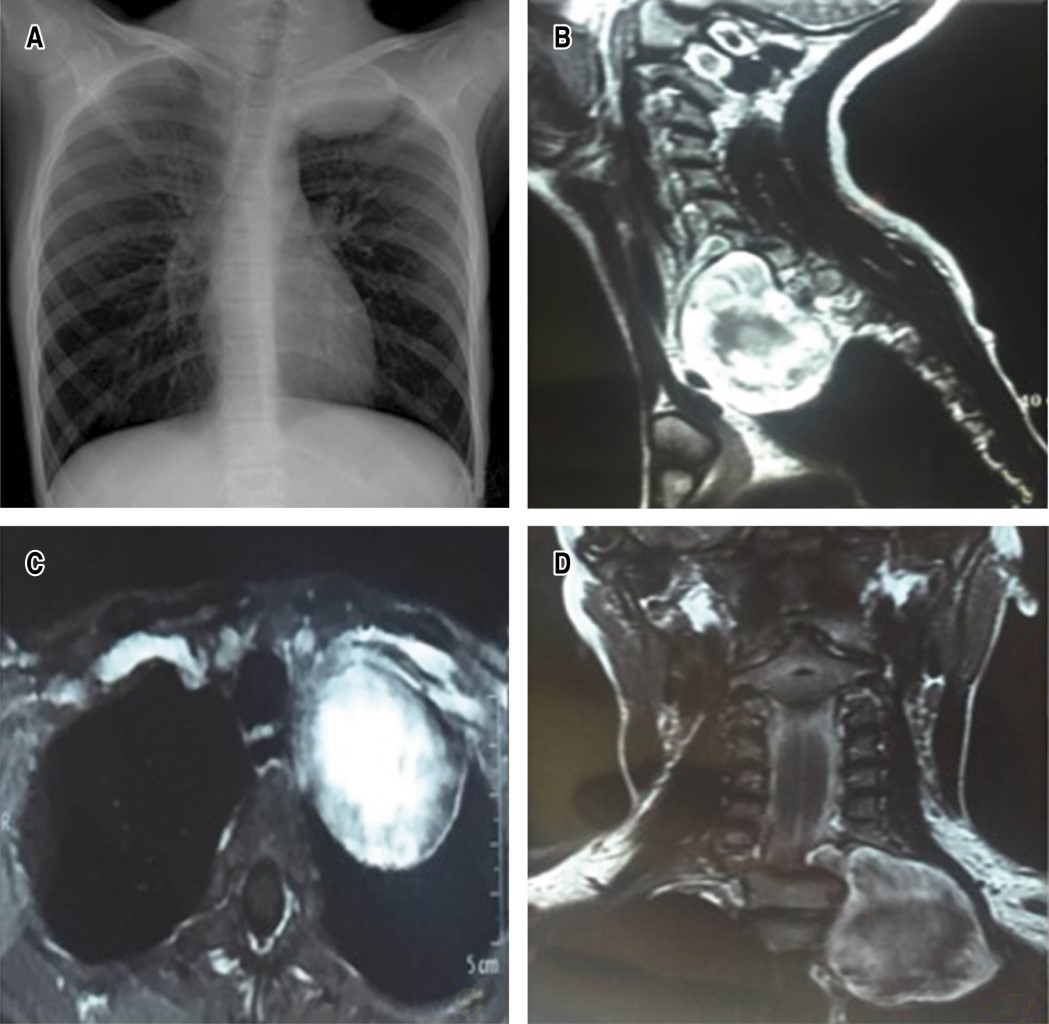

La resonancia magnética muestra lesión extradural que se origina a nivel de agujero de conjunción C7-T1 izquierdo, ensanchamiento y extensión rostral hacia cuello y desplazamiento de tráquea y esófago y en contacto con vaina carotídea e invasión hacia región mediastinal ipsilateral. Se realiza electromiografía en la que se observa disminución de la amplitud de latencias sensorial y motora del nervio cubital izquierdo (Figura 1A-D).

La ultrasonografía Doppler color y la tomografía podrían mostrar que los nervios ingresan excéntricamente al schwannoma, lo que a su vez no se observa en el neurofibroma (principal diagnóstico diferencial y pronóstico); sin embargo, los schwannomas son iso a hipointensos en T1 e hiperintensos en T2 de la resonancia magnética con gadolinio, definiendo las relaciones anatómicas preoperatorias como protocolo de estudio del plexo braquial y el sulcus torácico.5,6 No obstante, la consistencia dura e invasiva de la lesión asociada a síntomas sistémicos con adenopatías podrían proponer la biopsia por aspiración con aguja fina, una alternativa para predecir un diagnóstico final. En nuestro caso, la asociación diagnóstica con neurofibromatosis tipo I orientó hacia la plexopatía braquial por schwannoma.2